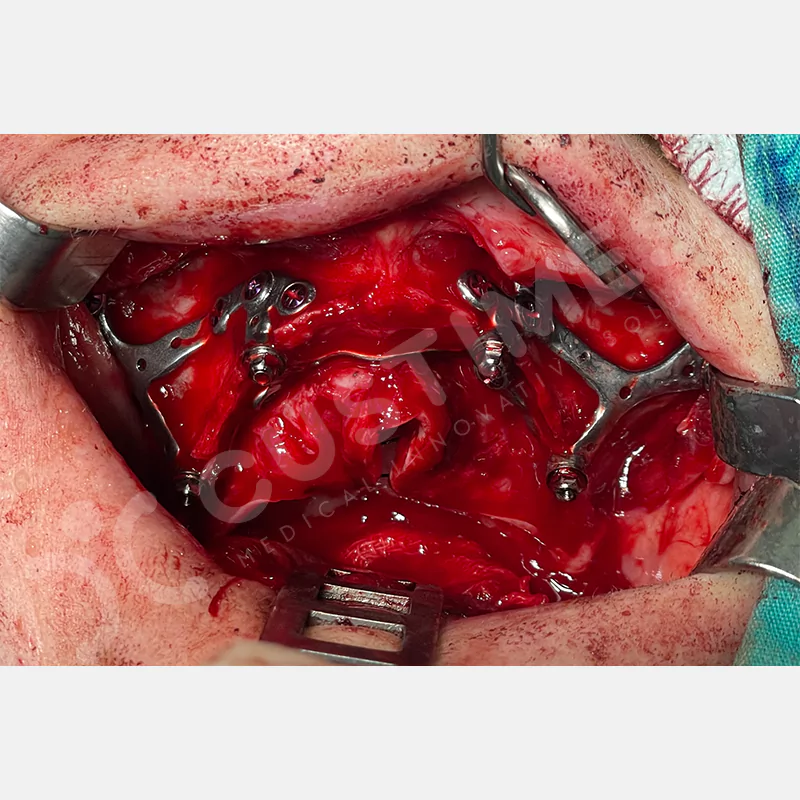

Modern diş hekimliğinde, çene gelişimini tamamlamamış veya ciddi kemik kaybı yaşayan hastalar için kişiye özel titanyum implantlar ile çözüm bulunmaktadır. CAD/CAM teknolojisi ve lazer sinterleme yöntemiyle üretilen bu implantlar, hastanın bireysel anatomik yapısına tam uyum sağlayarak geleneksel implantların uygulanamadığı vakalarda mükemmel bir alternatif oluşturmaktadır. Özellikle ileri derecede kemik kaybı olan hastalar için geliştirilen subperiosteal implantlar, periostun altına yerleştirilerek minimal invaziv bir yaklaşım sunarken, bilgisayarlı tomografi verileri ve sonlu eleman analizleriyle optimize edilmiş tasarımları sayesinde hem estetik hem de fonksiyonel sonuçlar garanti etmektedir. Bu yenilikçi teknoloji, tek seansta implant ve protez uygulamasına imkan vererek hastaların aynı gün doğal gülüşlerine kavuşmalarını sağlarken, kemik greftleme gibi ek işlem ihtiyacını ortadan kaldırarak cerrahi süreci büyük ölçüde kolaylaştırmaktadır. Kişiye özel tasarımı ve üstün biyouyumluluğu sayesinde, daha önce tedavisi mümkün görülmeyen kompleks vakalarda bile başarılı sonuçlar sunan bu implantlar, modern diş hekimliğinde yeni bir çağ açarak hastaların yaşam kalitesini artırmayı hedeflemektedir.

VAKA 2